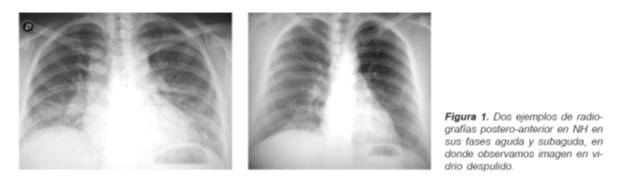

Las imágenes radiográficas en las diferentes formas de la NH, se caracterizan por el tipo de opacidad y distribución de la misma.

En la forma aguda se observan opacidades en vidrio despulido y un patrón nodular fino (1 a 3 mm) mal definido en forma bilateral y difusa, rara vez se encuentran imágenes reticulares finas y consolidaciones de los lóbulos inferiores focales hasta en un 10 a 25% (Figura 1).

En las etapas subagudas el patrón retículo nodular se vuelve más prominente con acentuación de estructuras broncovasculares y las formas crónicas se caracterizan por fibrosis con retracción de los lóbulos superiores, con opacidades reticulares gruesas, bronquiectasias centrales y pérdida de volumen con imagen en «panal de abeja» que representa el proceso cicatrizal.

Recalcando que las principales opacidades radiográficas que vamos a observar en la NH son reticulares o retículo nodulares que en varias ocasiones van a definir el patrón en panal. La presencia de sombras anulares que pueden llegar a tener un diámetro hasta de 4 cm suelen ocurrir debido a la presencia de bronquiectasias, bullas o quistes, todas estas imágenes las vemos en general en forma central con una distribución hacia los lóbulos superiores del pulmón. Actualmente se cuenta con otras técnicas diagnósticas como la tomografía de alta resolución, que ofrecen una mejor ayuda para el diagnóstico (10). Lo que ha hecho que la sensibilidad de la radiografía de tórax disminuya. Es importante considerar que la radiografía convencional de tórax puede ser normal hasta en el 20% de los casos agudos y subagudos, la razón de este hallazgo se desconoce, aunque se sugiere que los granulomas son tan pequeños o tan escasos y la neumonitis tan sutil como para ser aparentes en la radiografía, en donde habitualmente observamos imágenes. Por ello la tomografía de tórax de alta resolución (TCAR), método más sensible para evaluar el parénquima pulmonar comparativamente con la radiografía convencional de tórax, facilita el diagnóstico aún en casos sutiles de la enfermedad.